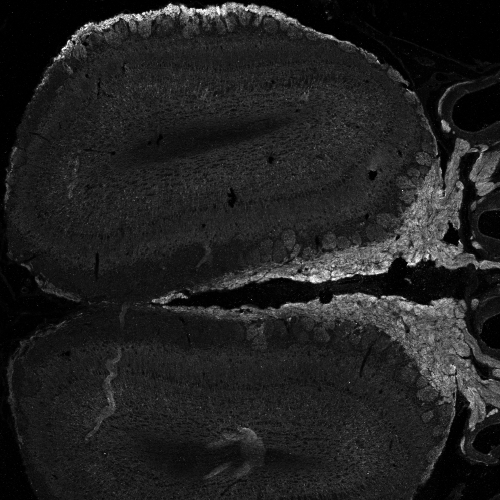

IHC Results Frozen section of Olfactory bulb from transcardially PFA-perfused Mouse shows strong staining of axon bundles (right side middle, figure 1) and moderate peripheral staining outside the glomeruli (top, figure 1). NCAM2 (red) is stained complementary to VGLUT2 (blue) and NQO1 (green) in figure 2. Recommended concentration: 0.5µg/ml. Paraffin embedded Human Brain (Cortex). Recommended concentration: 3.75ug/ml. This antibody has been successfully used in IHC in the following papers, PMID: 37724425 and PMID: 32043120. | |